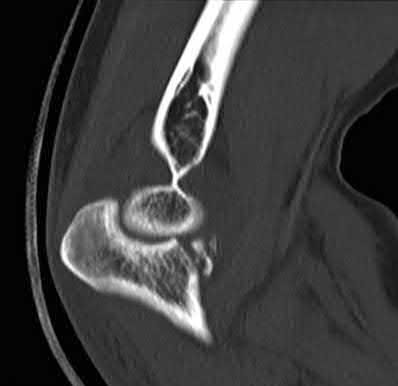

Question 2

A 28-year-old male sustains a severe hyper-dorsiflexion injury to his ankle in a motor vehicle accident, resulting in a Hawkins Type III talar neck fracture. Which of the following arteries provides the predominant blood supply to the body of the talus, placing it at significant risk for avascular necrosis in this injury?

Explanation

The artery of the tarsal canal, which is a branch of the posterior tibial artery, provides the dominant blood supply to the talar body. In a Hawkins Type III fracture (talar neck fracture with subtalar and tibiotalar dislocation), the blood supply from the artery of the tarsal canal, the artery of the sinus tarsi, and capsular vessels are disrupted, leading to an avascular necrosis (AVN) rate approaching 100%.